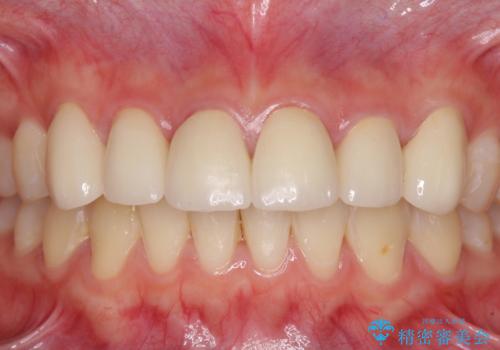

- コンポジットレジンによる治療で継ぎ接ぎだらけになってしまった前歯を綺麗にしたいとのことで来院された患者様です。

必要に応じて根管治療を行い、前歯6歯をオールセラミッククラウンで補綴することとしました。

治療途中に出産を迎えるため、下顎前歯のデコボコを部分矯正で改善し、上下前歯を綺麗に仕上げることとしました。

普段は海外在住であり、出産のための一時帰国を利用して短期集中治療を行いました。

自身の出産で大変な時期にもかかわらず、スケジュール通りに通院いただき、望まれたとおりの口元に仕上げることができました。